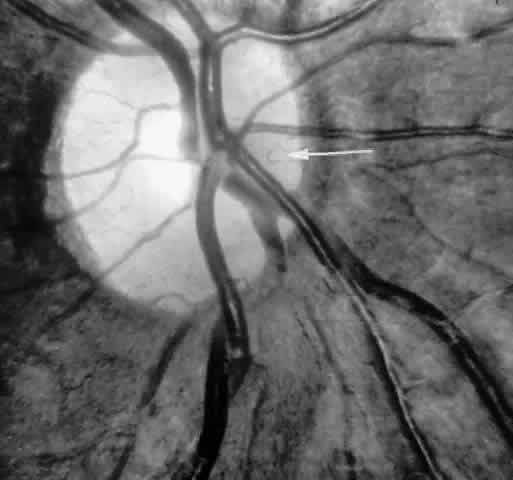

STAGE II: PERIPHERAL ARTERIOLAR-VENULAR ANASTOMOSES. Following occlusion of the terminal arterioles, anastomotic channels form to channel the blood from the occluded arteriole to the nearest venules. These anastomoses form at the interface between the perfused and nonperfused retina. Most likely, they are dilated preexisting capillaries rather than new vessels, since they do not leak on fluorescein angiography. The redirection of blood flow is probably due to hydrostatic forces (Figs. 22 and 23).

Fig. 22. A. Photograph of the peripheral retina, demonstrating capillary occlusions and exudate at the margin of perfused retina. B. Fluorescein angiogram of irregular capillary border, with capillary stumps extending into nonperfused retina and an arteriolar-venular anastomosis demonstrating stage II retinopathy.

Fig. 23. Fluorescein angiogram of continuous arteriolar-venular anastomosis demonstrating stage II retinopathy. (Note that this is the same eye demonstrating the qualitatively abnormal peripheral capillary border in Figure 25.)